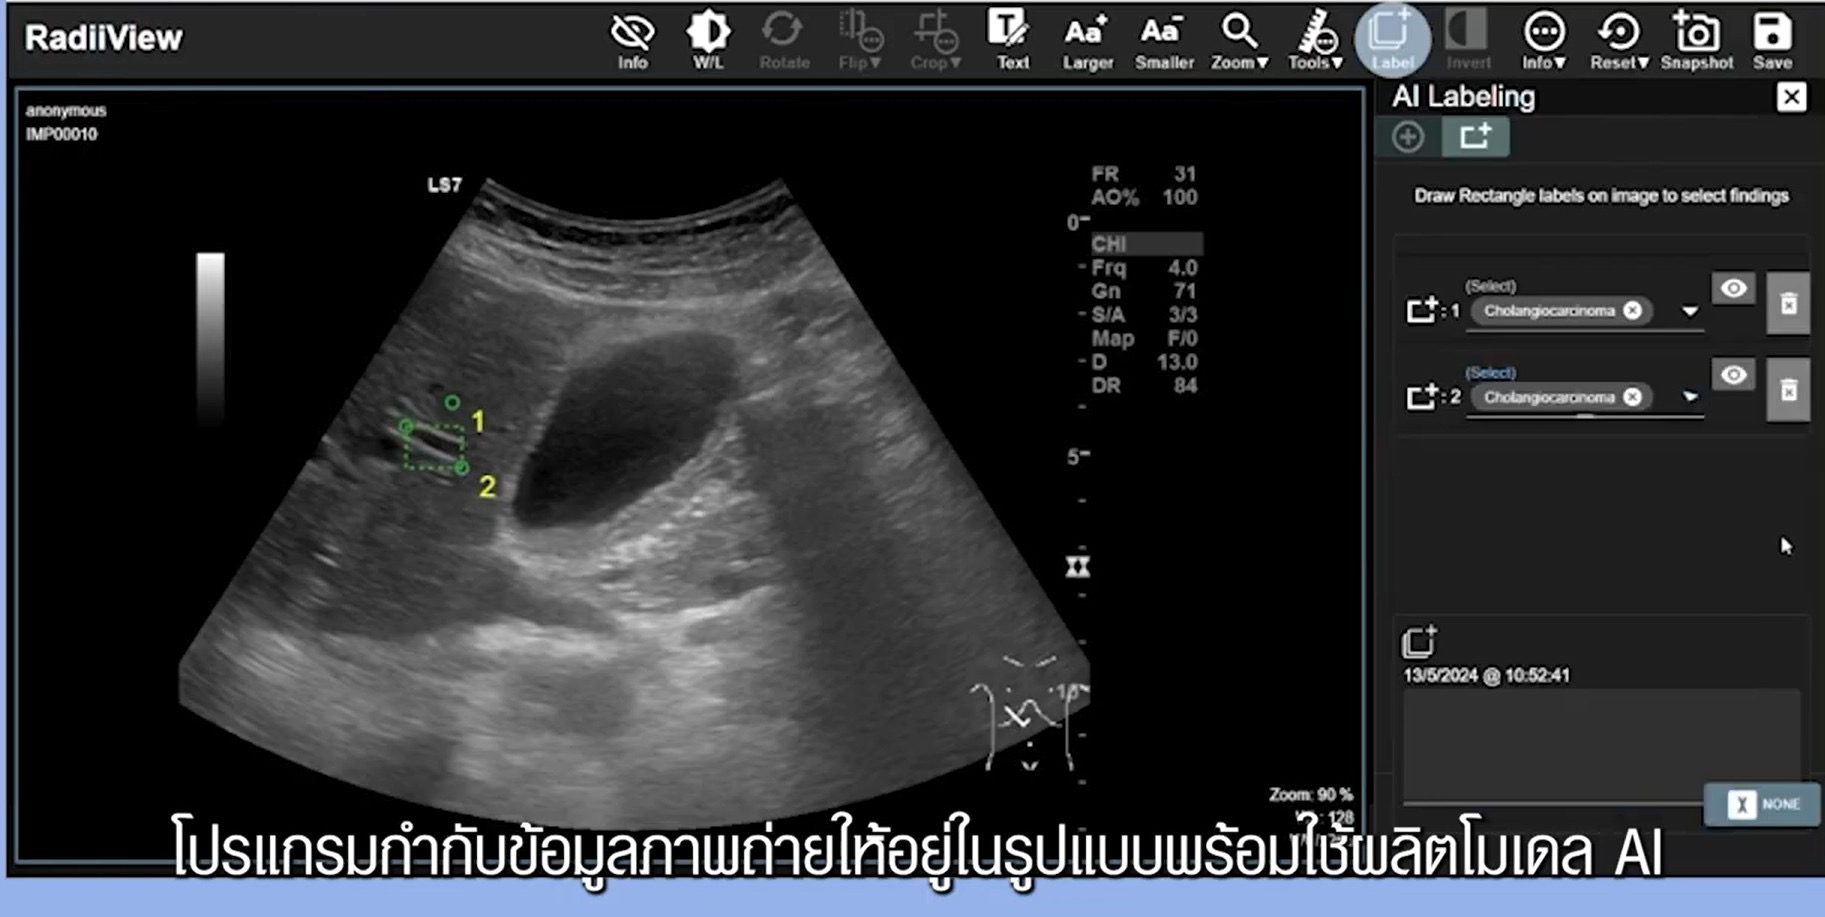

1. ส่วนบริหารจัดการข้อมูล (Data Management) รองรับการรวบรวม จัดเก็บ จัดทำรายการข้อมูลภาพทางการแพทย์อย่างปลอดภัยและเป็นระบบ มีการกำกับดูแลสิทธิ์การเข้าถึงตามหลักธรรมาภิบาลข้อมูล นอกจากนี้ นักวิจัยเนคเทค สวทช. ยังพัฒนา RadiiViewซอฟต์แวร์และคลาวด์แอปพลิเคชันสำหรับการกำกับข้อมูลภาพทางการแพทย์ (Annotation) ที่มีเครื่องมือช่วยให้แพทย์ระบุลักษณะสำคัญบนภาพได้อย่างแม่นยำ เพื่อสร้างชุดข้อมูล